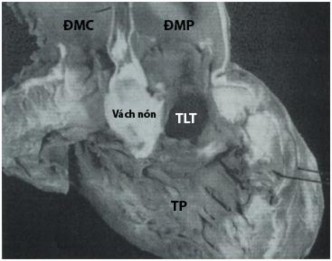

TLT dưới van ĐMP chiếm tỷ lệ khoảng 30% tổng số các bệnh nhân TPHĐR [1]. Đường kính của lỗ TLT thường không hạn chế (Hình 1.7). Lỗ thông nằm phía trên của hai ngành của dải băng vách và nằm phía dưới van ĐMP [64]. Trong trường hợp mào dưới van ĐMP tồn tại tạo thành bờ trên lỗ TLT, khoảng cách từ lỗ TLTtới van ĐMP tùy thuộc kích thước của mào dưới van ĐMP.

Hình 1.7: TPHĐR thể chuyển gốc động mạch. (A) TPHĐR với lỗ TLT dưới van ĐMP. (B) Minh họa TPHĐR với lỗ TLT dưới van ĐMP [39])